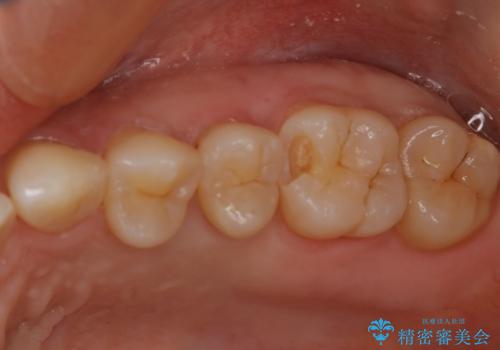

セラミックインレーは変色がなく耐摩耗性にも優れるため、長期的に良好な予後が見込める治療です。

セラミックインレー

歯の一部が虫歯になってしまった場合の治療法のひとつにインレーがあります。

虫歯になってしまった部分を含めて詰め物用に形を削り整え、型取りをし、出来上がってきた技工物をセメントで接着します。

自費治療では強度・色調・耐久性に優れたセラミックを使用した治療を選択する方が多いです。